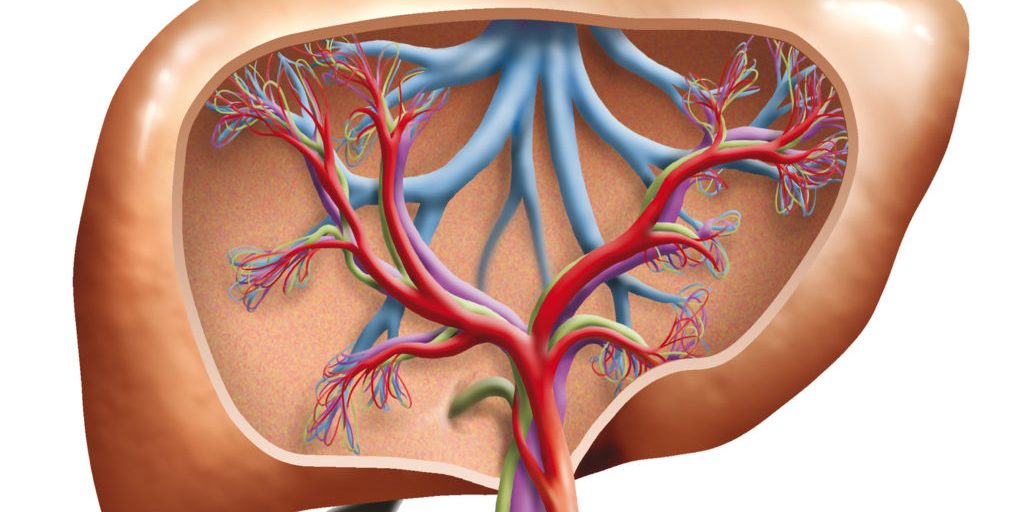

Die Entgiftung ist der natürliche Prozess des Körpers, nicht verwertbare Stoffwechselendprodukte, wie sie z.B. bei der Verdauung von Eiweiß im Organismus entstehen und toxische Stoffe, die von außen in den Körper gelangen, wieder auszuscheiden. Die Leber ist das zentrale Entgiftungsorgan und durch die Umweltbelastung in unserer heutigen Zeit besonders gefordert. Selbst bei einer gesunden Lebensweise nehmen wir über Luft, Wasser, Lebensmittel, Kosmetik- und Reinigungsprodukte oder Kleidung mehr Schadstoffe auf, als der Körper auf Dauer allein wieder ausscheiden kann. Vor allem giftige Metalle wie Nickel, Blei und Cadmium belasten die Leber sehr stark und sind in der heutigen Zeit zudem in zu großer Anzahl vorhanden. Zeolith kann aufgrund seiner speziellen Struktur einen großen Teil der Schwermetalle absorbieren und somit unschädlich machen. Zeolith unterstützt die Entgiftungsfunktionen des Organismus. Dadurch werden alle Stoffwechselprozesse und Funktionsabläufe unterstützt und Krankheiten vermieden.

Die Entgiftung ist der natürliche Prozess des Körpers, nicht verwertbare Stoffwechselendprodukte, wie sie z.B. bei der Verdauung von Eiweiß im Organismus entstehen und toxische Stoffe, die von außen in den Körper gelangen, wieder auszuscheiden. Die Leber ist das zentrale Entgiftungsorgan und durch die Umweltbelastung in unserer heutigen Zeit besonders gefordert. Selbst bei einer gesunden Lebensweise nehmen wir über Luft, Wasser, Lebensmittel, Kosmetik- und Reinigungsprodukte oder Kleidung mehr Schadstoffe auf, als der Körper auf Dauer allein wieder ausscheiden kann. Vor allem giftige Metalle wie Nickel, Blei und Cadmium belasten die Leber sehr stark und sind in der heutigen Zeit zudem in zu großer Anzahl vorhanden. Zeolith kann aufgrund seiner speziellen Struktur einen großen Teil der Schwermetalle absorbieren und somit unschädlich machen. Zeolith unterstützt die Entgiftungsfunktionen des Organismus. Dadurch werden alle Stoffwechselprozesse und Funktionsabläufe unterstützt und Krankheiten vermieden.

Unsere hauptsächlichen Entgiftungsorgane Leber und Nieren, aber auch Darm, Haut, Lunge und Lymphsystem sind in unserer belasteten Umwelt täglich stark gefordert. Es ist wichtig, sich das einmal bewusst zu machen. Denn auch wenn wir z.B. der Luftverschmutzung in der Regel nicht entgehen können, gibt es doch genug Bereiche, in denen es jeder selbst in der Hand hat, was er seinem Körper zusätzlich an Belastungen zumutet.